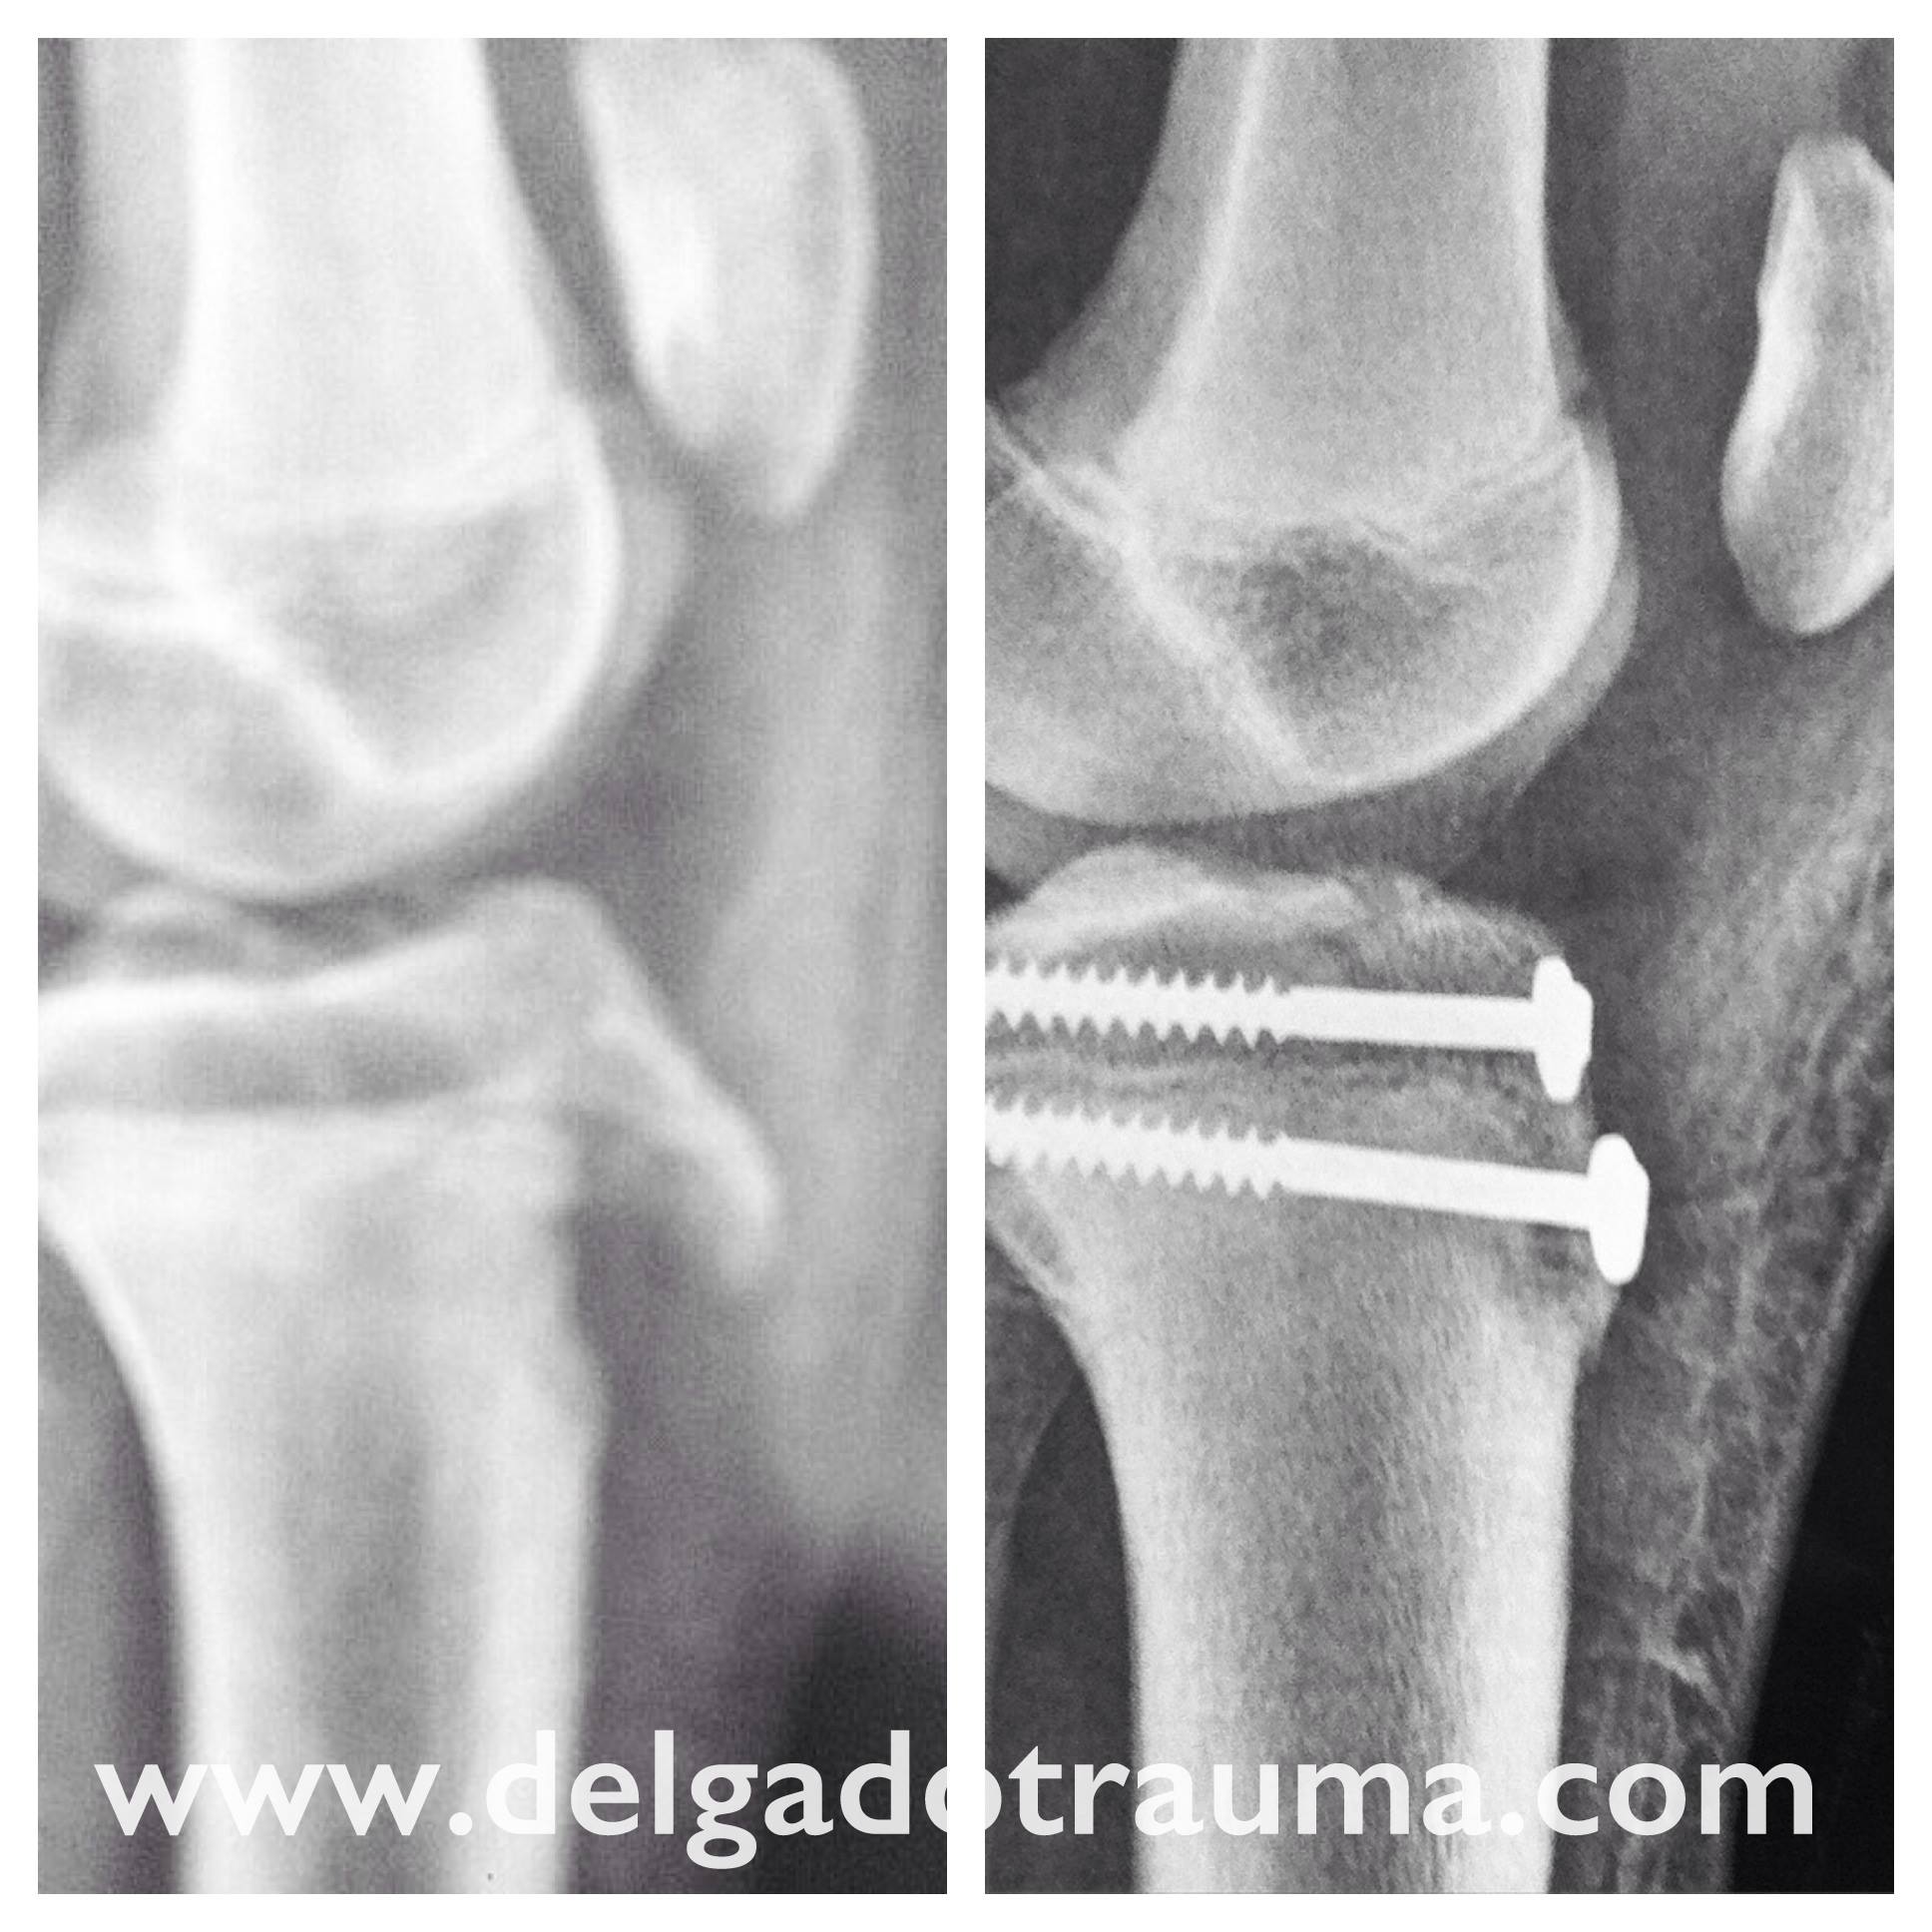

Algunos casos muy severos pueden requerir un breve periodo de inmovilización o incluso cirugía si se ha desprendido el hueso.

Si el traumatólogo lo considera oportuno le pedirá una radiografía para estudiar el estado del cartílago de crecimiento.